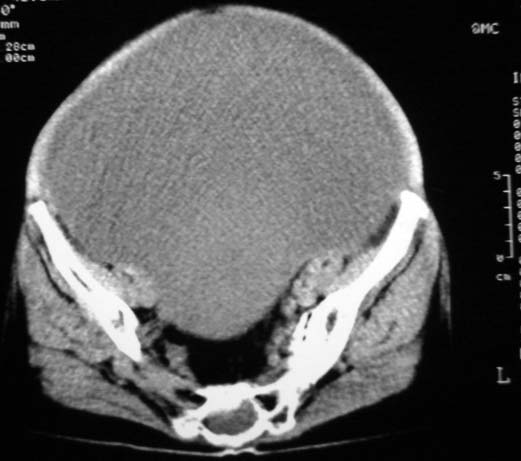

女,75岁,腹部胀大半年余,无其他症状。

考虑来源与卵巢的巨大囊腺瘤或囊肿。

真是腹大如牛,考虑卵巢巨大囊腺瘤或囊肿。

考虑来源卵巢巨大黏液性囊腺瘤。

手术结果http://www.radida.com/radinet/read.php?tid=40683